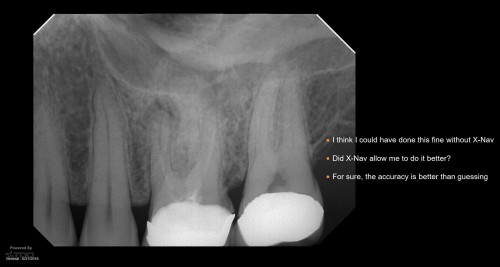

Because this was a Zirconia crown, my approach was to make a “staging platform” where I thought the access points would be. Proabbaly made the platform larger than I needed to. In this case, the X-nav was spot-on. I’m nowhere near Charles or Pushpak, but I am getting more comfortable with it. This took longer than I thought because I had to change the plan when we discoved the angles to get into the MB1 and MB2 required the handpiece to be “too vertical” and the cameras wouldn’t read them. So the angle of the dangle had to be altered during the procedure. Kind of a PIA….. gbc